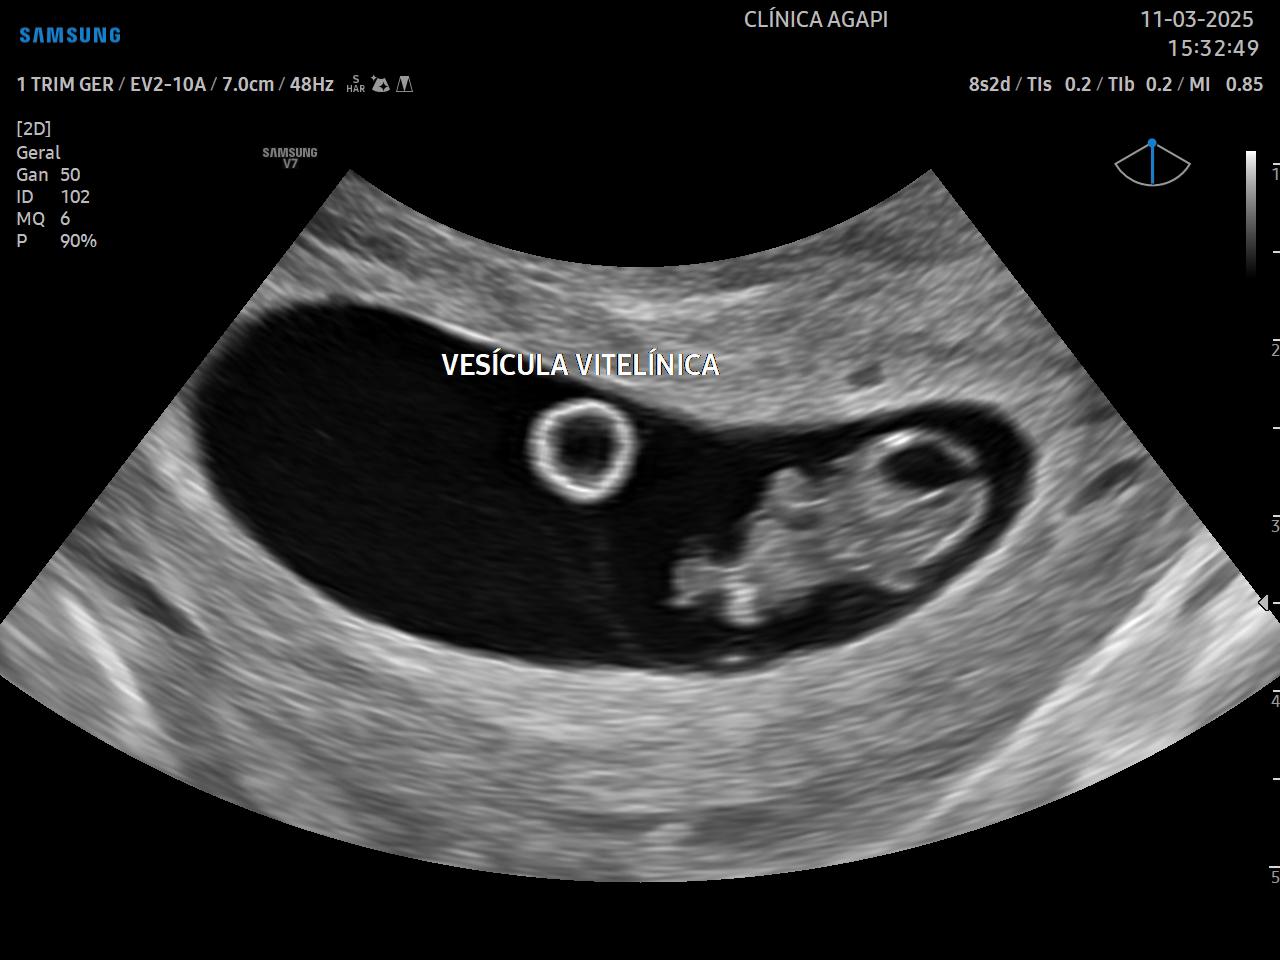

É o primeiro ultrassom da gestação e deve ser realizado preferencialmente após 7 semanas, porque nesse momento já é possível visualizar embrião e batimentos cardíacos. Quando feita próximo a 5/6 semanas, podemos visualizar somente saco gestacional e vesícula vitelínica, o que pode gerar ansiedade desnecessária.

Tem como objetivos avaliar a implantação do saco gestacional, determinar a idade gestacional, avaliar o número de embriões (se a gestação é única ou múltipla), determinar a viabilidade embrionária e buscar sinais de complicações ou mau prognóstico evolutivo.

Essa avaliação é realizada pela via transvaginal visando reduzir erros de cálculo de idade, tendo em vista que neste período as medidas são milimétricas.